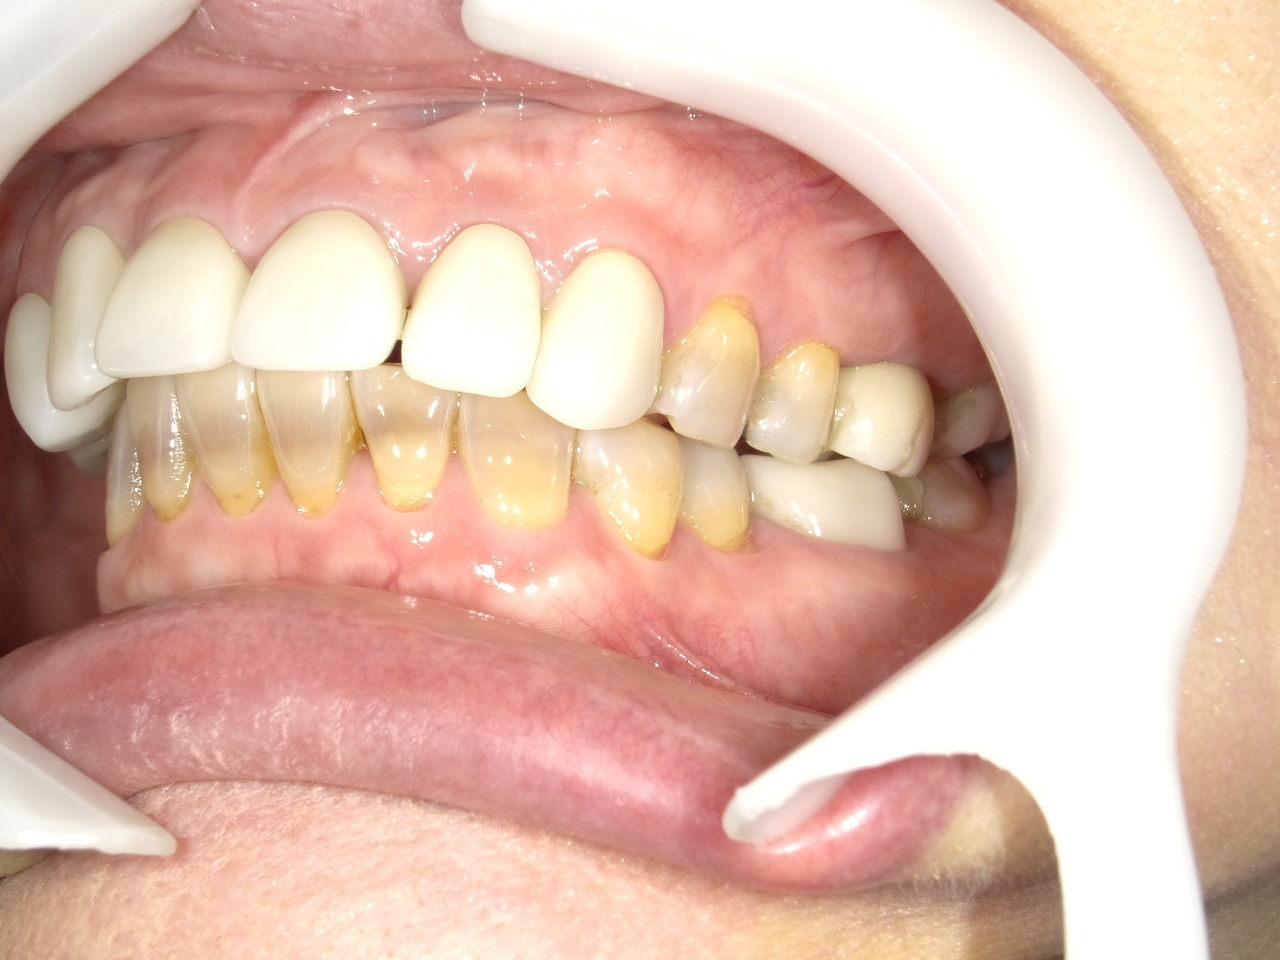

4.右上4~7番が重度に動揺しているために、抜歯した当日にインプラントを埋入して、3か月で最終的な歯を完成させたケース

Before

枚方市のインプラントの症例

After

K・S様 女性 60代

症状としては、 右上4から7番までのすべての歯の著しい動揺があり、食事が困難であった。

治療法としては、患者様は、患者様が3か月以内の治療完了を望んでいたために、炎症が若干あったが、右上4から7番ぼすべての抜歯を行い、右上4番(抜歯即時埋入)、右上6番(上顎洞までの骨がほとんどないため、グラフトレスサイナスリフト施行)にインプラントを1回法で手術を終え、2か月半後にインプラントの状態が安定したために、3か月で上部構造の、右上456のジルコニアブリッジを装着して、治療を終えています。

治療結果としては、抜歯したと同時にインプラントを埋入することで、抜歯した穴が自然に治る過程で、インプラントの骨結合と組織の治癒が同時に行われるために、3か月という治療期間で治療を終了することができたことと、機能面・審美面でも回復を行うができた。また、右上6番に関しては、グラフトレスサイナスリフトを行うことで、従来のサイナスリフトに比べ、約9か月早く治療を終えることができました。

治療の期間・回数:約3か月、インプラント抜歯即時埋入から最終補綴物装着まで8回

治療の価格:792000円(税込)

治療費の内訳:インプラント基本料(フィックスチャー(メガジェンインプラントANYONE使用) 及び手術費用、投薬費用、レントゲン費用、インプラント上部費用(アバットメントおよびジルコニアクラウンの費用用)330000円×2 660000円(税込み)。オプション、抜歯即時埋入加算(人工骨費用を含まず)5500円×2 11000円(税込み)右上5ジル9コニアブリッジのポンテック費用 88000円 右上6グラフトレスサイナスリフト費用 33000円(税込み

治療のリスクや副作用:手術後に、痛みや腫れ、出血、合併症などを引き起こす可能性があります。噛む感覚がご自身の歯と異なる場合があります。見た目がご自身の歯と異なる場合があります。手術後にメインテナンスを継続しないと、インプラントが抜け落ちる可能性があります。